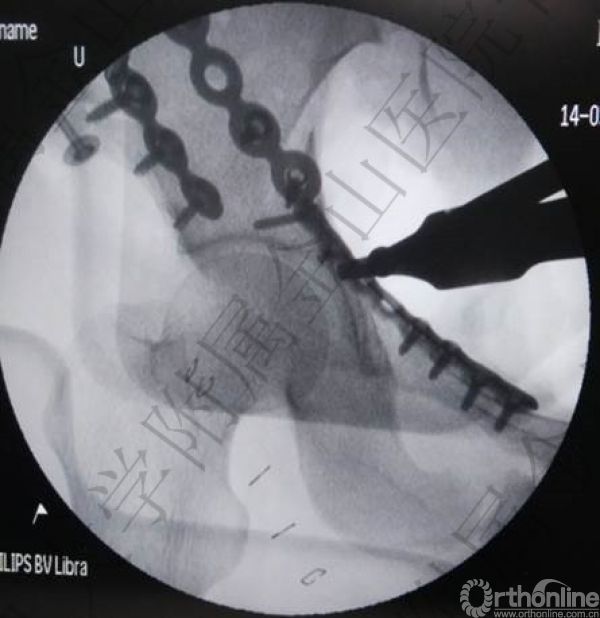

DSA:腹主动脉造影+双侧髂内动脉造影+栓塞术;

骨科:左侧骶髂关节脱位螺钉内固定术(稳定骨盆后环);